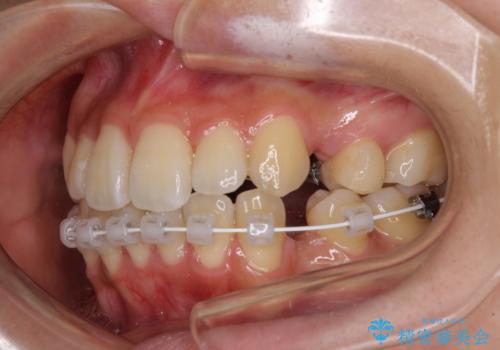

- ハーフリンガル

- 前歯のデコボコやクロスバイトと上顎の前突感による口の閉じにくさを気にして来院された患者様です。

目立たない装置を希望されたので、上顎が裏側装置のハーフリンガルを選択し、上下左右の小臼歯(計4歯)を抜歯して矯正治療を行うこととしました。

表側のワイヤー矯正に比べると治療期間は長く、費用も高額となりますが、どうしても目立たせたくないという方にはお勧めの抜歯矯正です。